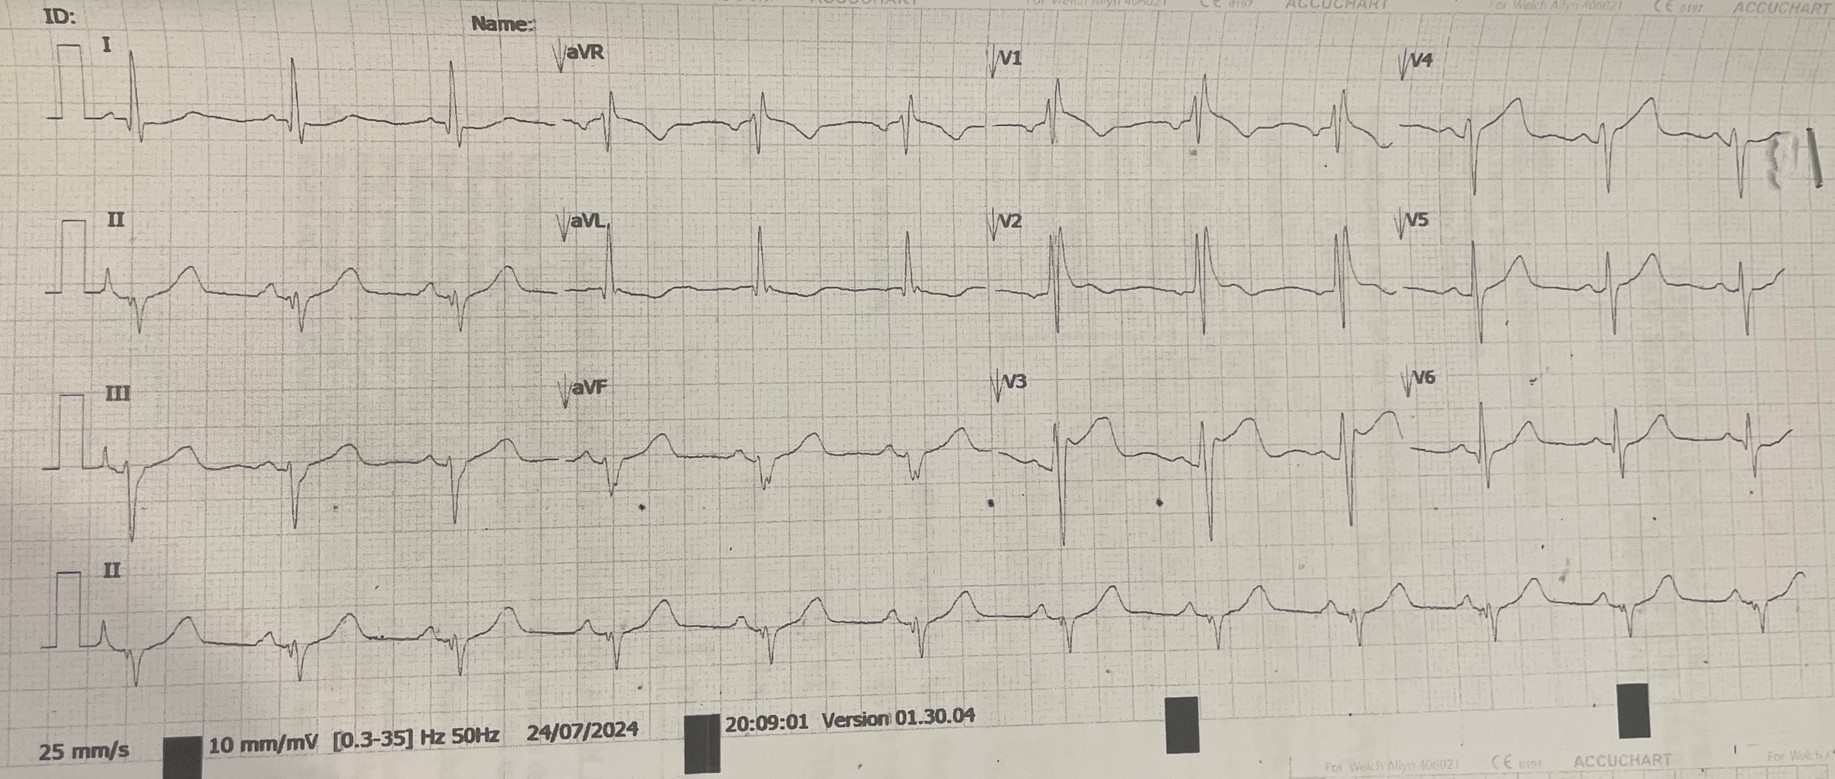

A case of a 44-year-old gentleman with epilepsy and coronary artery disease, who had angioplasty done to left circumflex artery with a DES in 2016. He complained of new onset of exertional angina for months and presented to hospital due to worsening symptoms. On presentation, he complained of ongoing chest pain, clinically not in failure with BP 100/62 mmHg, HR 74 bpm and SpO2 99% under room air. Lungs were clear, heart sound was normal with no murmur. ECG showed dynamic changes during chest pain.

Baseline ECG showed sinus rhythm with right bundle branch block. There were ST depression over lead I, aVL, V5 and V6 during chest pain. Laboratory examination showed creatine kinase level of 161 U/L (<200 U/L). Echocardiogram showed good LV systolic function, LVEF 65-70% with no RWMA, normal chamber size. He was treated for unstable angina and underwent in-hospital coronary angiography (CAG) and percutaneous coronary intervention (PCI) in view of recurrent angina.